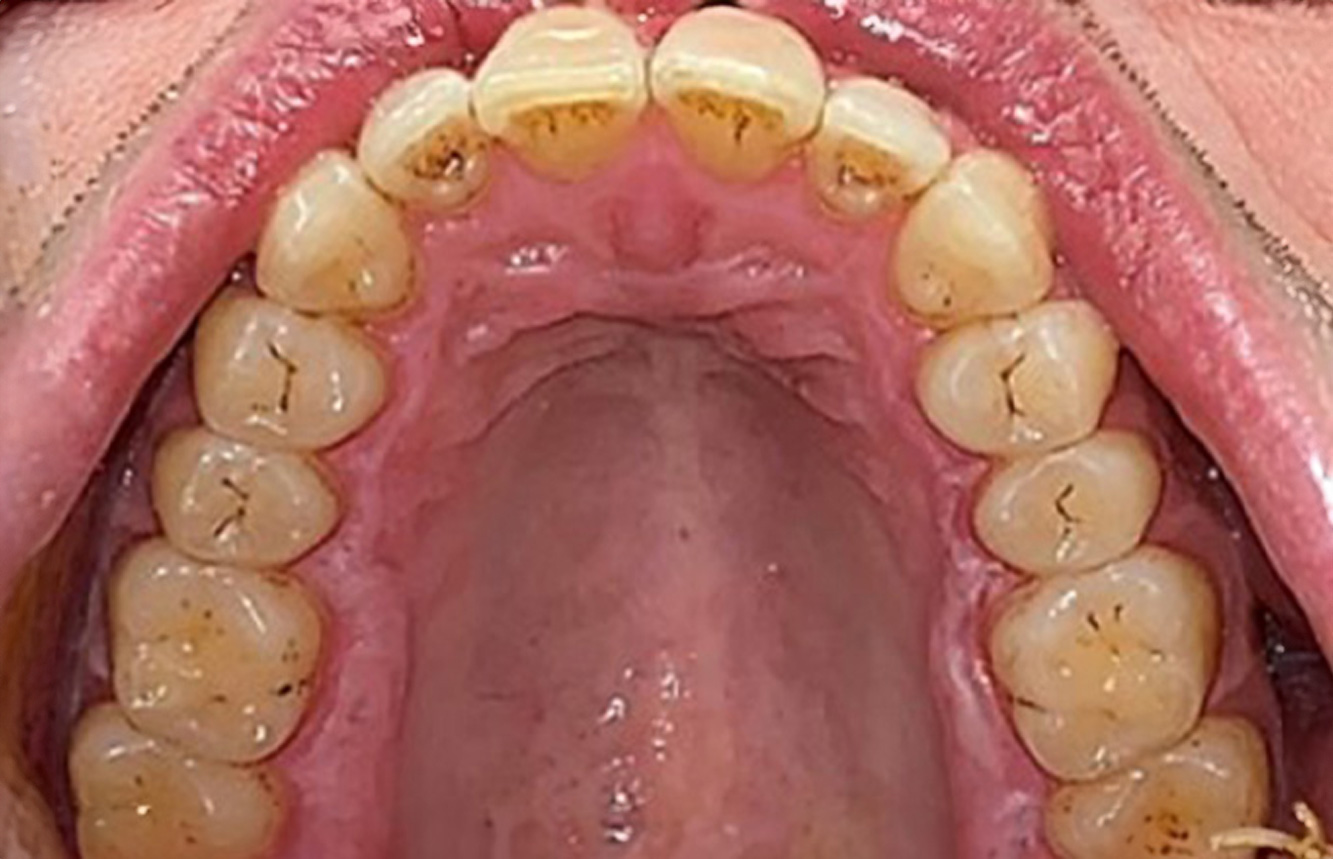

Case presentation: Complex Dental Prosthesis Management

The direct relationship between intraoral and general health, as well as the bidirectional influence that they may have on one another, is well-known (1,2). It is absolutely essential to consider both factors when planning preventive intraoral measures and treatment in the dental practice. The primary objective is the maintenance of patient health and quality of life from both dental and medical perspectives. more